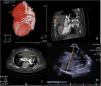

On arrival, he was hemodynamically stable and still under the effect of a new oral anticoagulant. Surgery was postponed enabling a washout of the anticoagulant. Meanwhile, labetalol was initiated for blood pressure control and a cardiac CT (Figure 1A–C) and a transthoracic echocardiogram were performed. The diagnosis was established as a large ascending aorta pseudoaneurysm which had already eroded the sternum. Also, a cavity posterior to the stentless valve with communication to the left ventricle outflow tract, which caused moderate periprosthetic leak, was described.

(A–C) Preoperative cardiac computed tomography (CCT). (A) Three-dimensional reconstruction showing the ascending aorta false aneurysm. (B) Two dimensional (2D) sagittal plane; yellow arrows: pseudoaneurysm eroding through the sternum; red arrow: periprosthetic posterior cavity. (C) 2D axial plane, yellow arrows: extrinsic main pulmonary artery compression due to pseudoaneurysm. (D) Intra-operative transoesophageal echocardiography (CT); yellow arrow: sizing of pseudoaneurysm (102 mm).

Two bleeding points were identified in the aortic wall (aortic cannulation and antegrade cardioplegia sites) and the rest of the aortic wall was reasonably preserved and had a normal diameter. The hypothesis of local infection and the complexity of a complete replacement of the aorta, of the previous prosthetic valve and eventually coronary reimplantation in a prosthetic conduit was considered too high risk a procedure. Two bleeding points were corrected with direct buttressed sutures (Teflon pledgets) (Figure 2A). Short periods of low flow and circulatory arrest were used to enable visualization and correction of the bleeding points. CBP was discontinued after warming and the sternum was closed. Total CPB time and circulatory arrest was 194 minutes and 7 minutes, respectively. TOE (Figure 1D and video 1) was performed intra-operatively and regarding the pseudoaneurysm, the surgical outcome was positive.

Post-operatively the patient progressed well. Empirical antibiotics (vancomycin, gentamicin, and rifampicin) were initiated. He was extubated on the second postoperative day and was transferred to the ward on the fourth day. Postoperative transthoracic echocardiogram and chest CT (Figure 2B) demonstrated a good surgical result. Microbiological and pathological analysis were negative for active infection, so antibiotics were discontinued after 21 days. The patient was transferred to this local hospital on day 13. TOE performed one month after surgery still described a periprosthetic leak in relation to a posterior cavity in the aortic root. A few months later, the patient underwent transcatheter closure of the perivalvular leak with good result.